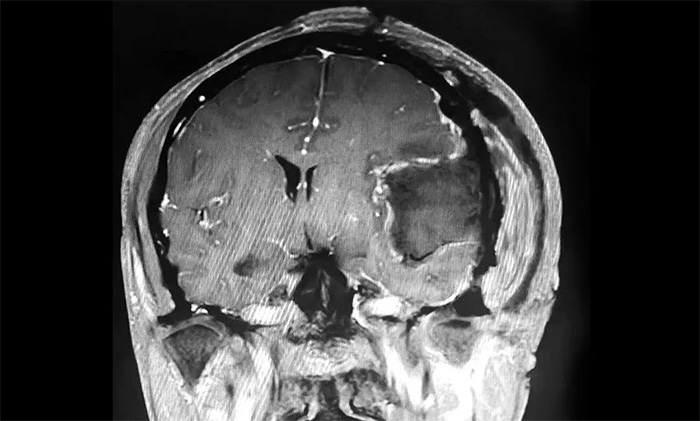

▲ 肿瘤顺利切除

手术取左侧额颞顶部入路,在显微镜下,沈建康主任与于耀宇主任通力协作,仔细分离肿物周边密集的神经血管,逐步分块切除肿物及附着的硬膜。切除肿瘤后,术区瘤腔未见活动性出血。历时5小时,手术顺利完成,留取病理标本送检。

术后,患者生命体征平稳,安返监护病房。经对留取的肿物样本进行病理分析,确定为纤维型脑膜瘤(WHO 1级),为良性肿瘤。